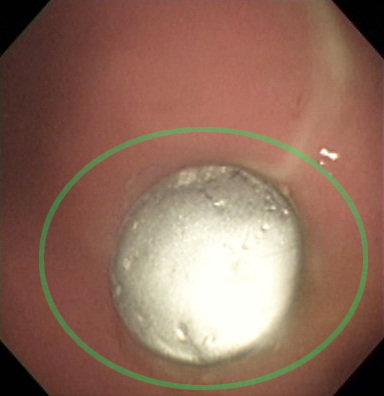

下の写真は、洋服のボタンを誤飲してしまった犬での内視鏡検査で、胃の中に1個のボタンが確認できました(緑丸)。

胃内に銀色に光るボタンを確認